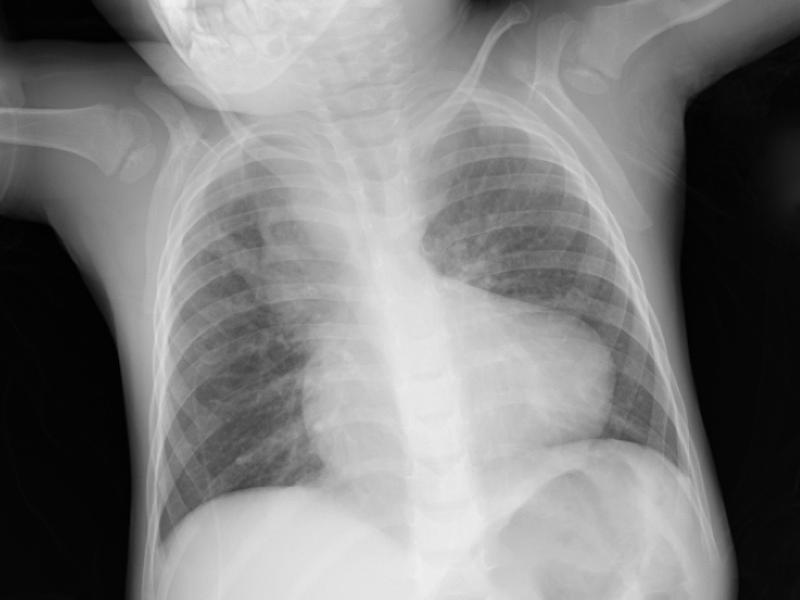

An 18-month-old male presents with his parents who have